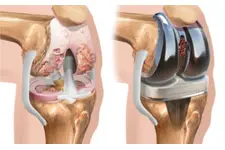

Diz kıkırdak aşınması, diz eklemindeki kıkırdak dokusunun zamanla bozulması ile ortaya çıkan bir durumdur. Yaş, aşırı kullanım, yaralanmalar ve obezite gibi faktörler bu durumu tetikler. Belirtiler arasında ağrı, sertlik ve hareket kısıtlılığı yer alır. Tedavi yöntemleri ise ilaç, fiziksel terapi ve cerrahi seçenekleri içermektedir. Bu yazıda, diz kıkırdak aşınmasının belirtileri, nedenleri ve tedavi yöntemleri detaylı bir şekilde ele alınmaktadır.

Diz Kıkırdak Aşınması Belirtileri ve Tedavisi Diz kıkırdak aşınması, diz ekleminde bulunan kıkırdak dokusunun zamanla bozulması ve incelmesi durumudur. Bu durum, genellikle yaşlanma, aşırı kullanım, yaralanmalar ve obezite gibi faktörlerden kaynaklanmaktadır. Kıkırdak, eklemler arasında amortisör görevi görerek, kemiklerin birbirine sürtünmesini önler. Kıkırdak aşınması, dizdeki ağrı, sertlik, şişlik ve hareket kısıtlılığı gibi belirtilerle kendini gösterir. Bu makalede, diz kıkırdak aşınmasının belirtileri, nedenleri ve tedavi yöntemleri üzerinde durulacaktır. 1. Diz Kıkırdak Aşınmasının Belirtileri Diz kıkırdak aşınmasının belirtileri, hastalığın ilerlemesine bağlı olarak değişiklik gösterebilir. Genel olarak görülen belirtiler şunlardır:

4. Tedavi Yöntemleri Diz kıkırdak aşınması tedavisi, hastanın durumuna ve aşınmanın derecesine bağlı olarak değişmektedir. Tedavi yöntemleri şunları içermektedir: